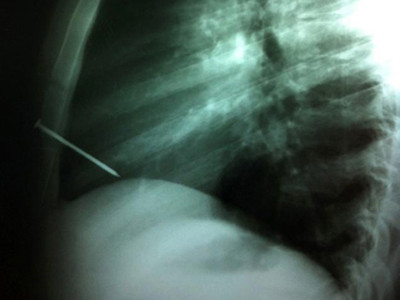

Kết quả chụp X-quang cho thấy chiếc đinh đã đâm thẳng vào khoang tim của bệnh nhân. Sau 2 tiếng phẫu thuật, các bác sĩ mới lấy được chiếc đinh ra.

| Ảnh chụp X-quang chiếc đinh đâm vào tim người thợ mộc. Ảnh: Nydailynews. |

Người thợ mộc 19 tuổi ở Argentina đã được đưa đến bệnh viện El Cruce Néstor Kirchner ở thủ đô Buenos Aires đầu tuần trước sau khi bị một người đồng nghiệp vô tình bắn chiếc đinh vào lồng ngực bằng súng bắn đinh.

Kết quả chụp X-quang cho thấy chiếc đinh đã đâm thẳng vào khoang tim của bệnh nhân. Các bác sĩ đã tiến hành phẫu thuật và lấy chiếc đinh ra khỏi lồng ngực sau 2 tiếng.

Giám đốc điều hành Arnaldo Medina cho biết nhóm bác sĩ đã không gỡ chiếc đinh ra ngay lập tức vì nó có thể ảnh hưởng đến sức khỏe của người bệnh. Trả lời trên tờ La Nacion, bác sĩ Marcelo Nahín nói: "Trong phòng mổ, chúng tôi tiến hành mở lồng ngực một cách rất cẩn thận để tránh nguy cơ đụng phải chiếc đinh và khiến vết thương bị lớn hơn. Khi đã nhìn thấy chiếc đinh rồi, chúng tôi mới từ từ rút nó ra khỏi tâm thất phải của bệnh nhân. Hiện tại cậu ấy đã phục hồi rất tốt".